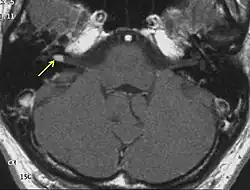

МРТ головного мозга. Невринома слухового нерва указана стрелками

МР-картина небольших размеров невриномы слухового нерва после введения контрастного вещества

На МРТ выявляется ровный контур опухоли и по её периферии полоска сигнала так называемой «ликворной щели», деформация мозжечка и ствола головного мозга. При распространении невриномы во внутренний слуховой проход внекананальная её часть имеет вид «свисающей капли»[30].

Приблизительно 2/3 неврином выглядят гипоинтенсивными, а одна треть изоинтенсивными на Т1-взвешенных томограммах. На Т2-взвешенных томограммах невриномы характеризуются повышением сигнала, степень которого варьирует. Участки гетерогенно изменённого сигнала (вследствие образования кист) характерны для новообразований больших размеров (как правило, более 3 см). Все невриномы интенсивно накапливают контрастные вещества, более чем в 70 % случаев их накопление гетерогенно[30].